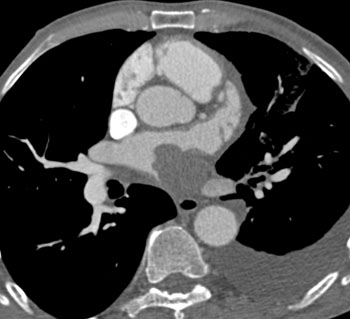

![]() | Question 17: 68 year old male with a history of non-small cell lung cancer with increasing shortness of breath and chest pain. What is the best diagnosis? |